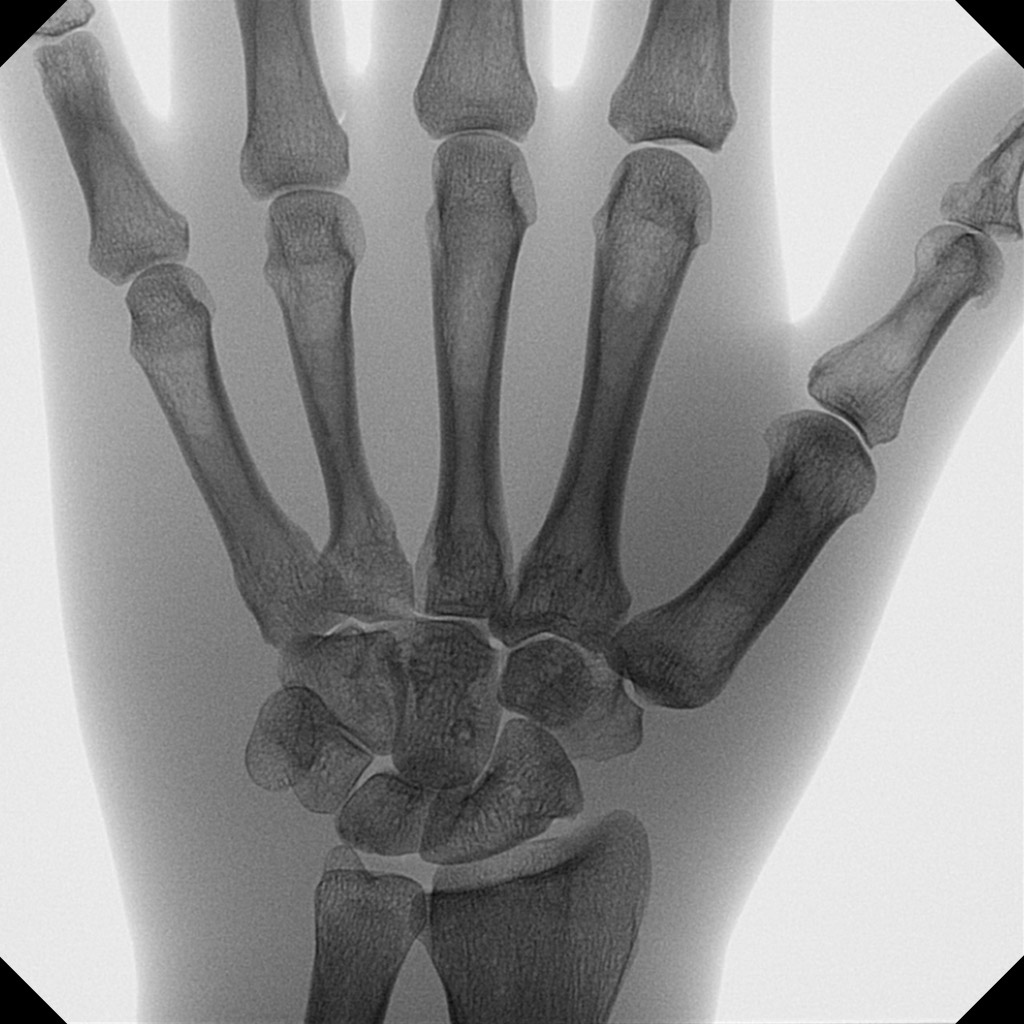

Les mini arceaux chirurgicaux améliorent considérablement la prise en charge des patients pour la chirurgie de la main et du pied.

Orthoscan propose dans ce domaine un portefeuille complet d’appareils avec fluoroscopie pulsée et capteurs plans ultramodernes, afin d’obtenir des images brillantes sans perte de qualité d’image, même pour des problèmes complexes.

Sur le TAU 2020 en particulier, le grand capteur permet de visualiser l’anatomie dans son intégralité afin de minimiser le nombre de prises de vue nécessaires. Des collimateurs motorisés à réglage continu limitent l’exposition aux rayonnements à la zone souhaitée.